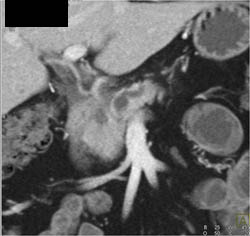

Hepatic Abscess and Pancreatic Tumor